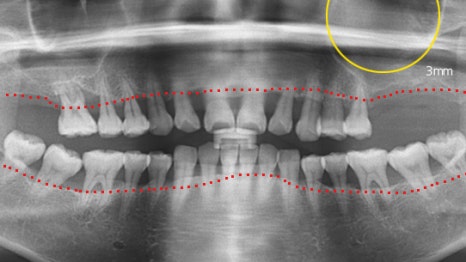

사례 3

교정 유지 장치를 활용한 임플란트

17개 임플란트를 권유받고 방문한 환자분의 경우,

치주 치료 후 앞니 흔들림이 개선되어 발치하지 않고

교정 유지 장치 를 활용하여 보완하였습니다.

기존 보철물을 제거하고 11개의 임플란트를

식립하여 치료를 마무리했습니다.

목동치과에서는 교정 치료와 협진을 통해

식립 개수를 줄이는 전략을 세웁니다.